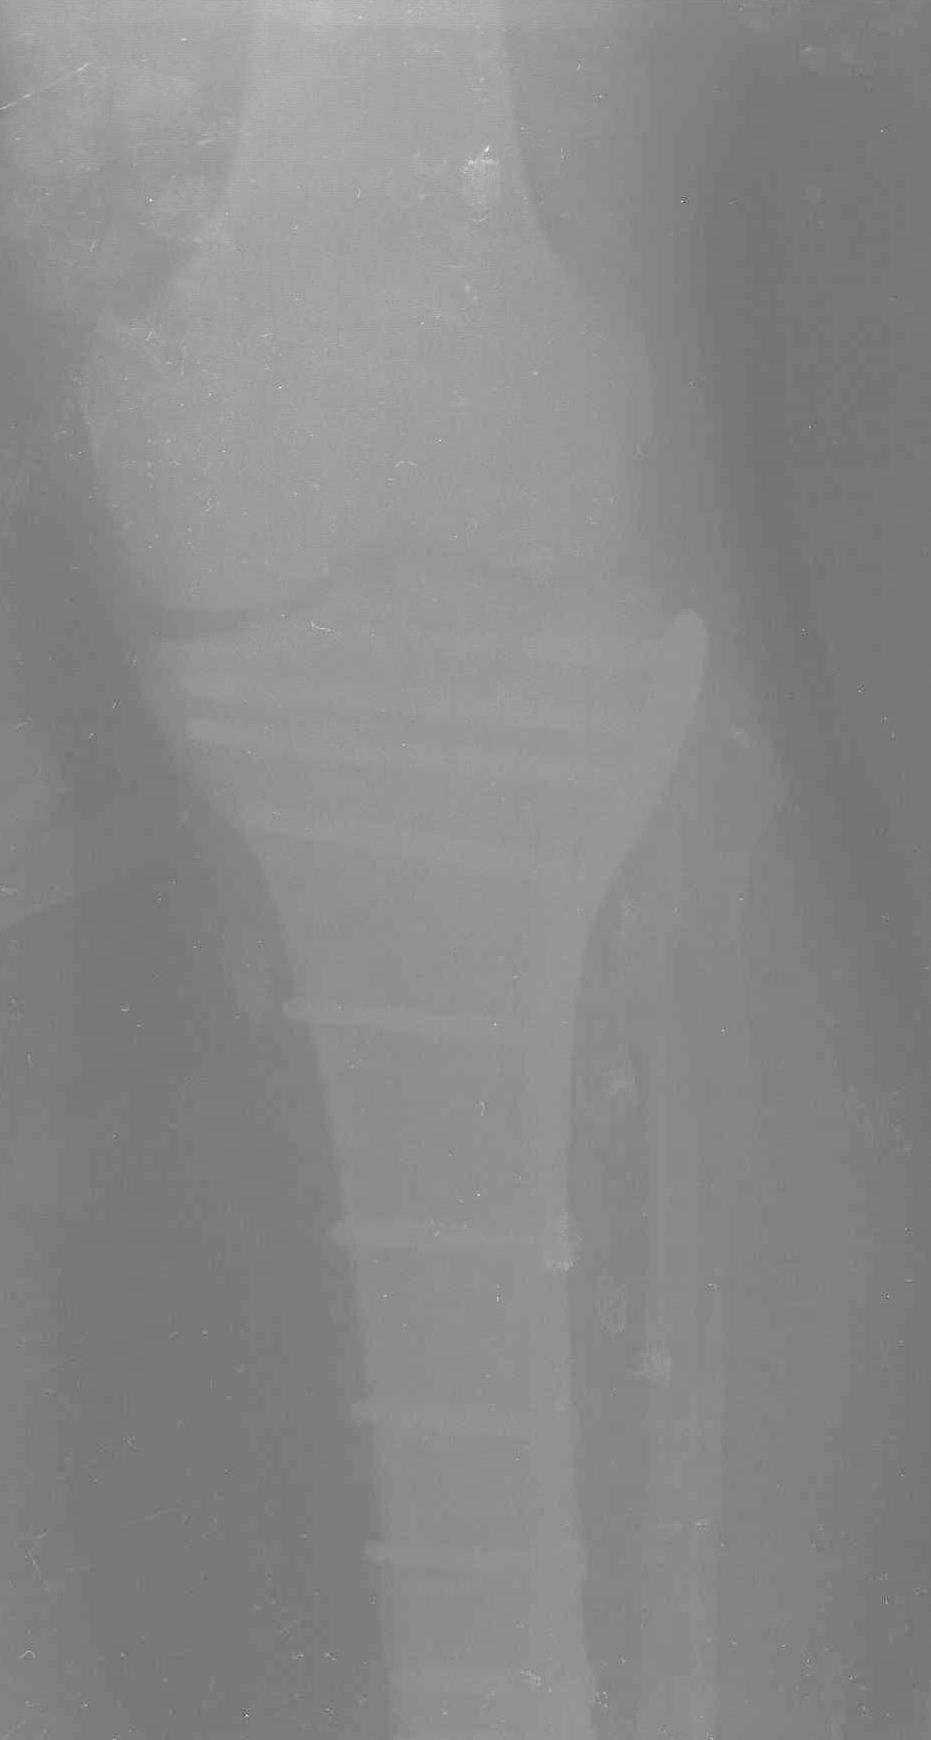

Трудно поверить, что разрекламированная Ортопедическая школа Восточной Украины позволяет такие странные снимки? На прямом снимке сохранен общий контур плато, но не известна судьба импрессии суставной поверхности. На полубоковой?, оставлен без репозиции задне-медиальный отдел, и навряд ли после такой фиксации можно удовлетвориться результатом.

Представленные снимки не информативны, нужны отдельные качественные снимки коленного сустава и голени без ротации.